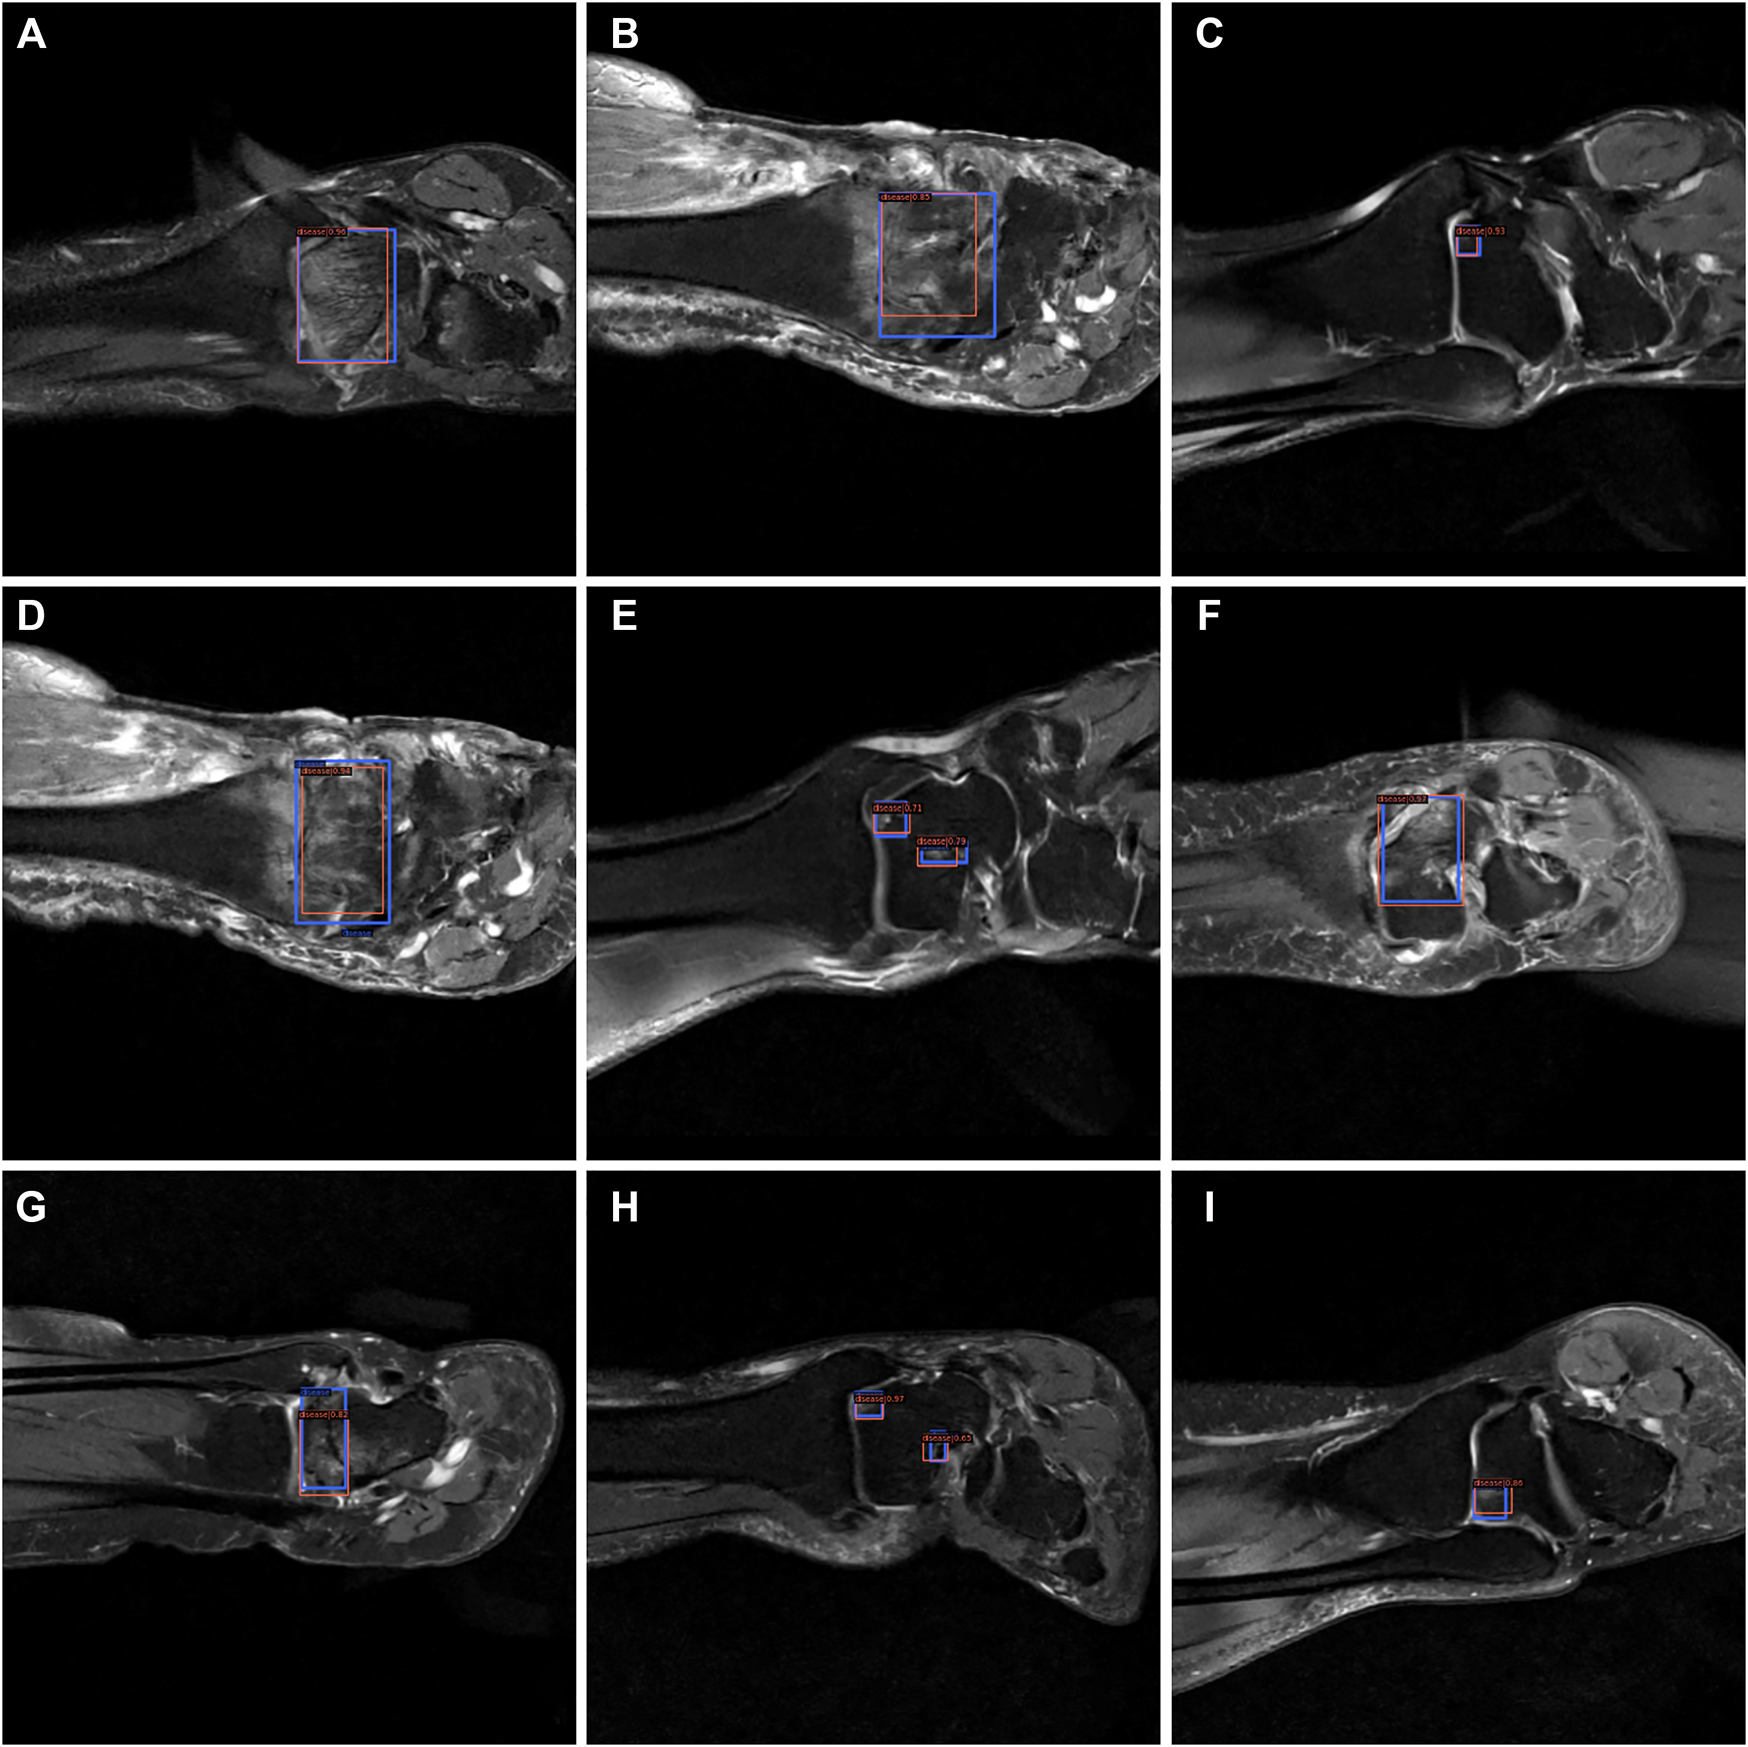

From Figures 7–9, we could intuitively observe that our network provided a comparable detection result (red bounding boxes) with that of senior radiologists (blue bounding boxes). Noticeably, our model achieved stable detection results on all three detection tasks, which shows the effectiveness of our method. More examples are shown in the Supplementary Figures S1–S3.

FIGURE 7

The bounding box visualization. Prediction result (red) vs. the ground truth (blue) of the osteochondral lesions. All the images (A–I) were selected from testing group to determine the AI recognition accuracy of ROI. AI detection result was labeled by red rectangular. The ground truth was manually depicted and labeled by blue rectangular.